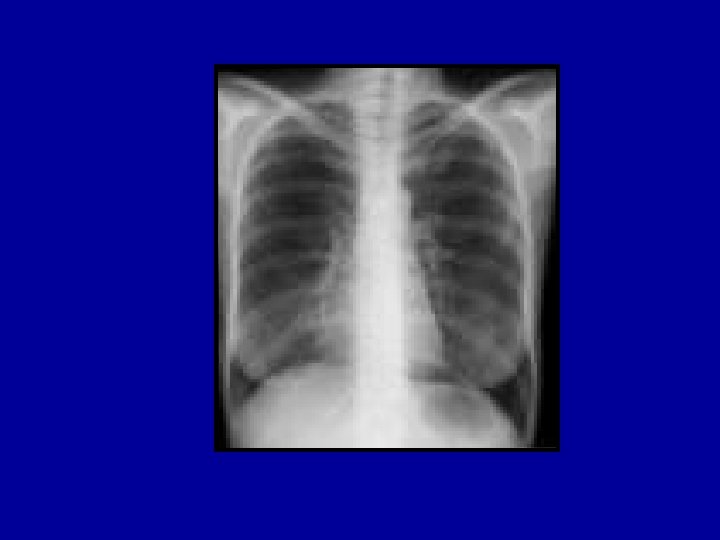

ARDS • A patient must meet all of the following: – Acute onset of respiratory symptoms – CXR with bilateral infiltrates – No evidence of left heart failure – Pa. O 2/Fi. O 2 < 200 mm Hg (regardless of PEEP) – American-European Consensus Conference on ARDS (Am J Resp Crit Care Med 149: 818, 1994) • The following are implied: – Previously normal lungs – Decreased lung compliance – Increased shunting – Hypoxemic respiratory failure